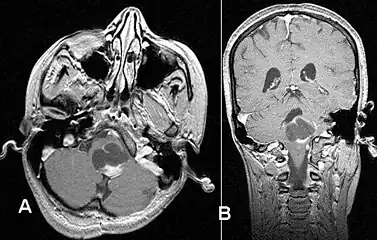

Pilocytic astrocytoma in the hypothalamic region.

Axial non-contrast CT in a nine-year-old girl showing a slightly hypodense mass in the tectum of the brainstem, compressing the aqueduct of Sylvius and causing obstructive hydrocephalus

T1-weighted coronal MRI image postcontrast showing heterogeneous contrast enhancement within the presumed tectal plate glioma